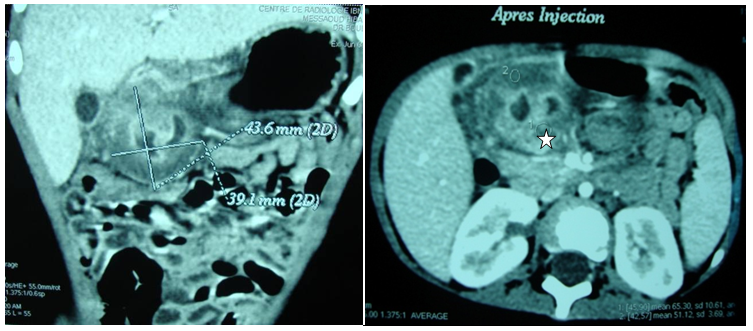

A two year old girl was presented in emergency for paroxystic abdominal pain without vomiting or other signs. The physical exam showed an epigastrium mass of 3cm which is round, tense, smooth and non tender beneath the umbilicus. Biologic exams were normal. Abdominal ultrasound with computer tomography revealed a cystic epigastric mass of 4.3cm with a wall that took contrast (Figure 3). Around this mass there was an ultrasound aspect of volvulus (Figure 4). A barium-meal examination demonstrated delayed gastric emptying through a narrowed pyloric antrum, which was distorted by a non communicating mass (Figure 5). At laparotomy, a cystic mass measuring approximately 4 × 3cm was identified anterior and lateral to the pyloric channel, sharing a common wall. The mass compressed the pyloric channel, resulting in partial gastric outlet obstruction. The duplication cyst did not communicate with the pyloric channel. Most of the cyst was excised, and the mucosa of the remnant cyst wall was cauterized. Histologic examination revealed gastric mucosa with a smooth muscle coat, which was consistent with a pyloric duplication cyst. No aberrant tissue was seen. The postoperative course was uneventful. The patient was asymptomatic 4years later.

Figure 3 Computer tomography: Cystic epigastric mass with a fine wall ( ☆ ) that took contrast.

Figure 4 Ultrasound aspect of volvulus around the mass.